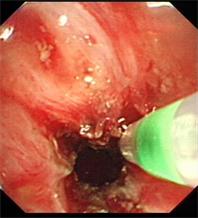

图片2 对狭窄处进行切割扩张